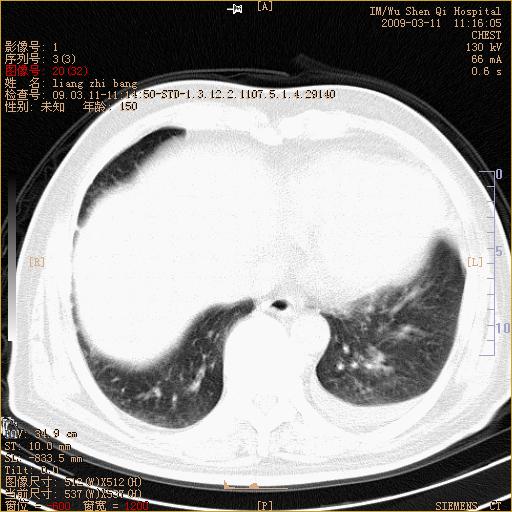

标题: CT18604:男,60岁,咳嗽一月余 [打印本页]

标题: CT18604:男,60岁,咳嗽一月余

1)考虑左肺上叶中央型肺癌并左肺上叶肺不张;建议必要时行纤支镜检查进一步明确诊断。2)左侧胸腔积液。

肺门肿块、支气管开口闭塞伴肺不张及胸水!典型的中心型肺癌变现!

1、左肺上叶中央型肺癌并上叶阻塞性肺不张。

2、左侧胸腔少量积液,右侧胸膜轻度增厚。

左肺们肿块并左肺上叶不张。考虑左肺中心性肺癌并左肺上叶不张及左侧胸腔积液